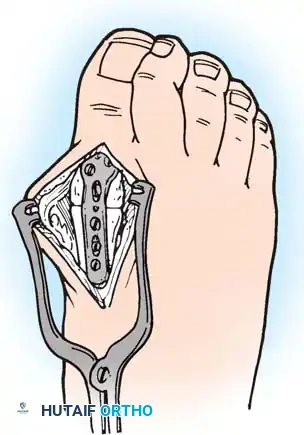

1. Approach: A dorsal longitudinal incision is made medial to the EHL tendon, extending from the mid-shaft of the first metatarsal to the interphalangeal joint.

2. Joint Preparation: The capsule is incised, and the collateral ligaments are released. The severely eroded articular surfaces of the first metatarsal head and the base of the proximal phalanx are resected. Cup-and-cone reamers are highly recommended to preserve length while allowing multi-planar adjustment.

3. Positioning: The hallux is positioned in 10 to 15 degrees of valgus and 15 to 20 degrees of dorsiflexion relative to the first metatarsal shaft. Neutral rotation must be confirmed to ensure the toenail faces directly dorsal.

4. Fixation: Rigid internal fixation is achieved using a dorsal contoured titanium plate and a lag screw across the arthrodesis site.

Fig. 81-2 (A, B) Preoperative clinical views showing severe dorsal subluxation-dislocation of lesser toes. (C) Plantar view post-resection of metatarsal heads. (D) Excellent postoperative clinical alignment following first MTP arthrodesis and lesser metatarsal head excision.